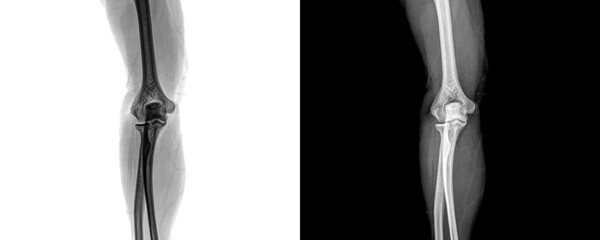

Podobny obraz Medical Elbow Anterior View X-Ray Radiograph Illustrating...